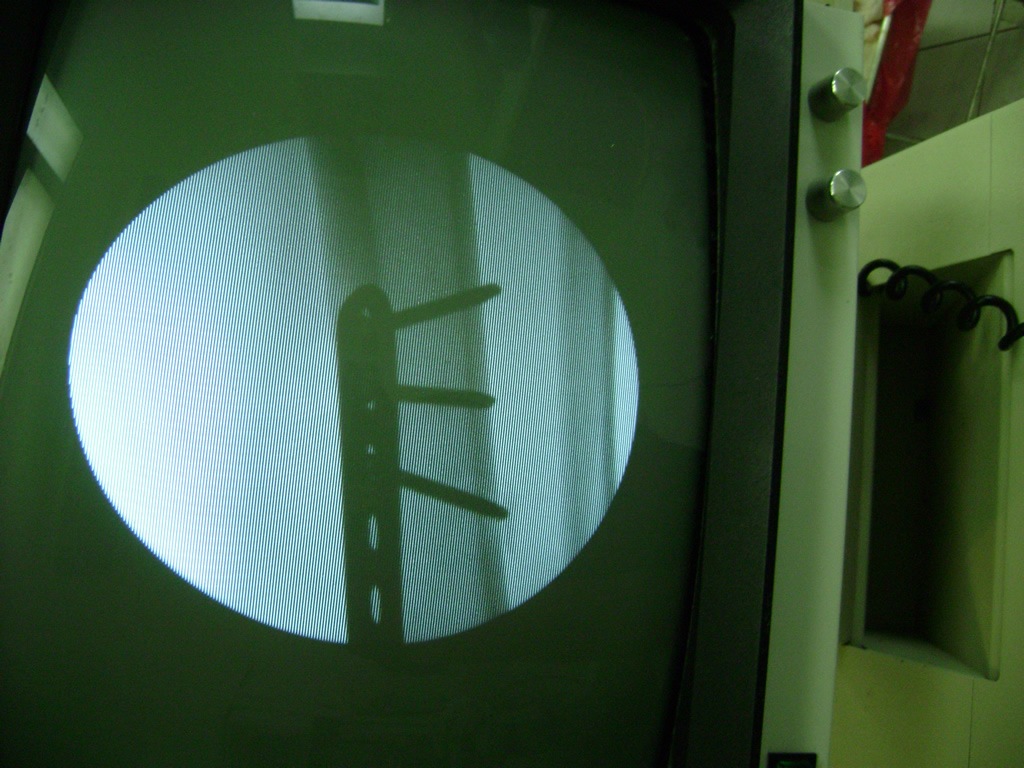

La mayor parte de las roturas implican a la parte proximal del hueso (parte del hueso próximo a la rodilla) o a la parte distal (parte del hueso cerca del tobillo).

Debido a la fina cobertura de piel que recubre la tibia y el peroné, las fracturas generalmente son abiertas, es decir, el hueso roto rasga la piel, atravesándola. Las fracturas de tibia y peroné generalmente se producen por un fuerte impacto o torsión.